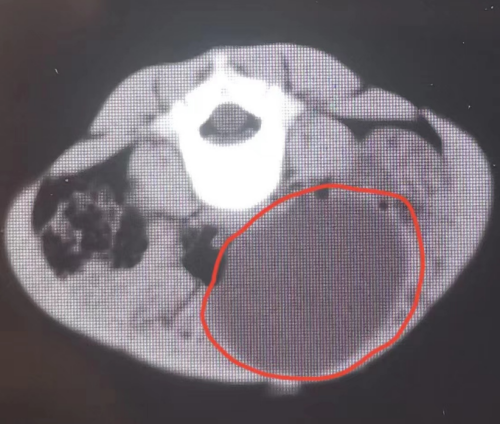

妇产科医生介绍,孩子左卵巢上长了一个直径达8cm的肿瘤,术后病理检查报告为良性畸胎瘤。患儿恢复良好,目前情况已稳定。

入院后,超声科副主任医师钟卓敏为雯雯仔细复查了腹部彩超,提示其左卵巢上长了一个直径约8cm的肿瘤。通常来说,卵巢肿瘤发病年龄越小,恶性肿瘤的可能性越大,而且雯雯半年前超声下肠套叠复位时还没有发现肿瘤,半年内长到了8cm,更应警惕卵巢恶性肿瘤可能。